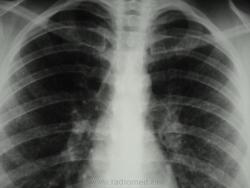

девушка 1985 г.р. дообследована после профилактической флюорографии, на КТ написали гистиоцитоз. Диагноз пока не подтвержден. Жалоб не предъявляет, курит в течение 8-9 лет. консультирована у фтизиатров, свою патологию они исключили.

На мой взгляд, выражены два компонента:

- преимущественно мономорфная диссеминации;

- интерстициальный компонент.

По рентгенограммам, создается впечатление превалирования "изменений", преимущественно, в средних и нижних отделах легочных полей.

Но, КТ, по всей видимости, свидетельствует, именно, о диффузности процесса, с некоторым превалированием в отдельных отделах.

Изменения диффузны. По rg более выраженны в нижних отделах, за счет марсива тканей. Ждем анализ мокроты и промывных вод.

И, хотя, по КТ, был выставлен гистиоцитоз, в первую очередь должен быть исключен или подтвержден "Его величество туберкулёз".

Очень на то похоже, что аналогия..."Более 90% больных гистиоциозом-Х (Лангергасоклеточным гистиоцитозом) - курильщики"...